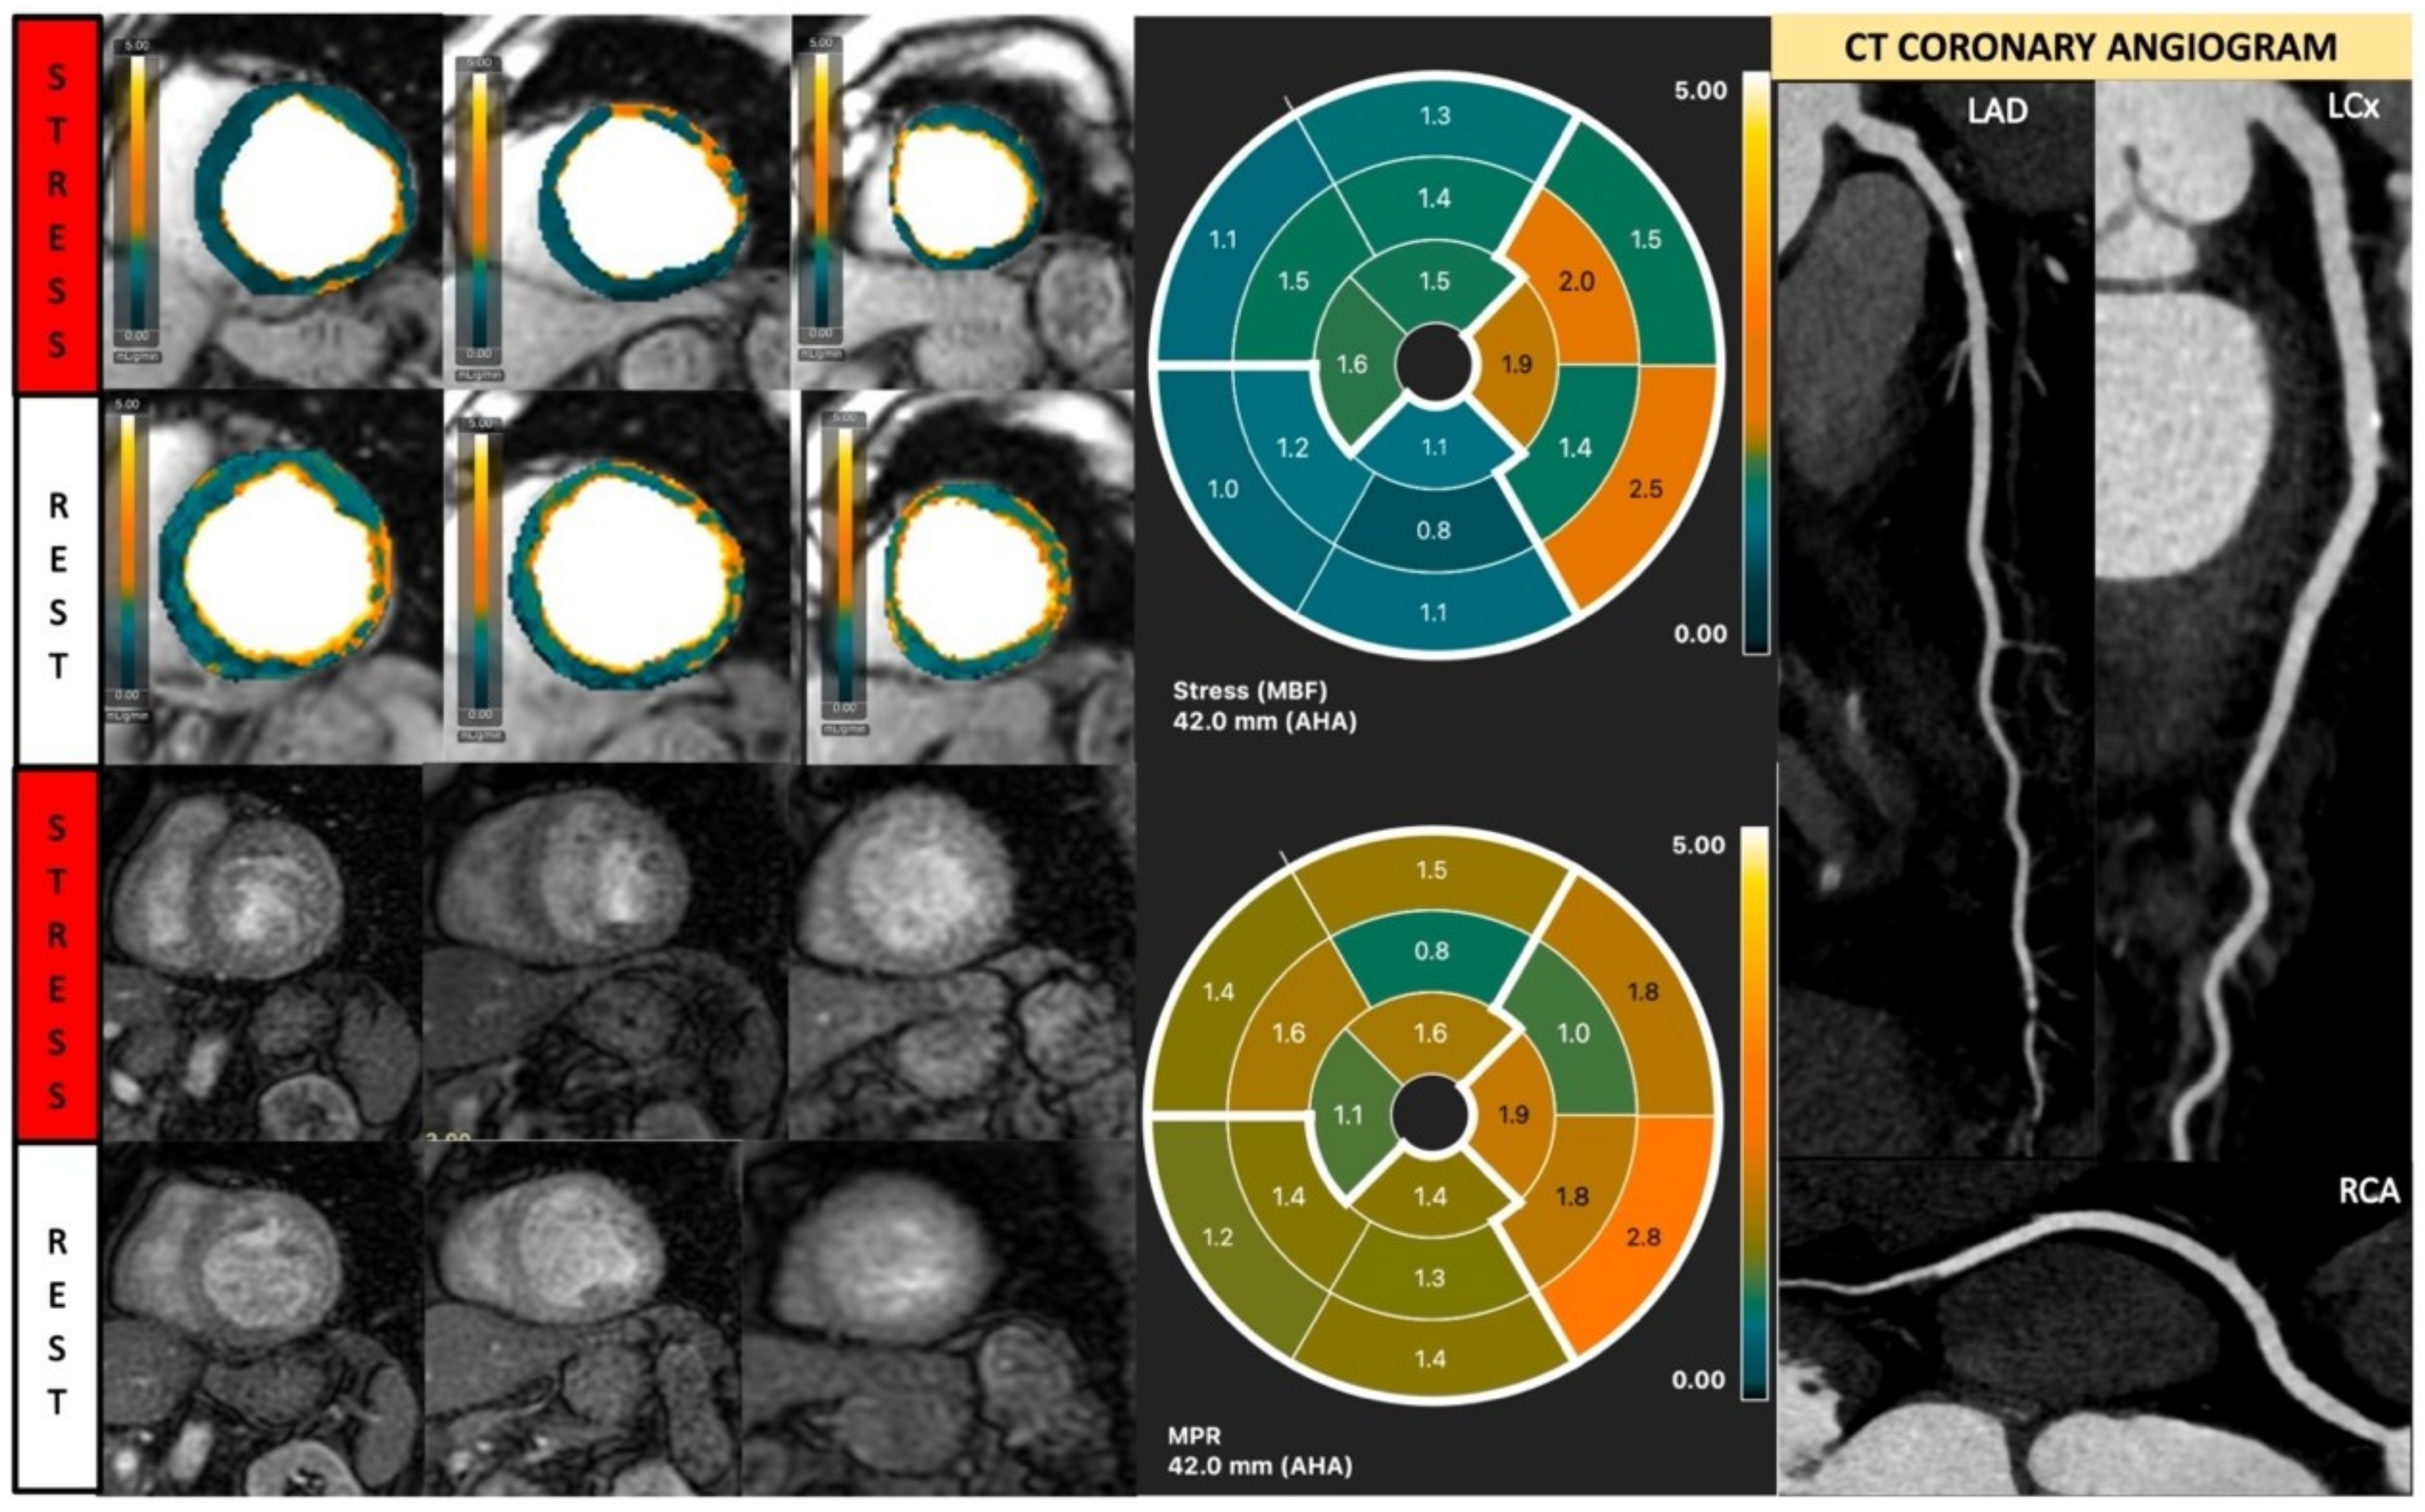

Fully quantitative analysis of myocardial blood flow (MBF) of significant CAD. Male, 55 years old, presenting with chest pain during hiking. CCTA showed chronic total occlusion in left circumflex artery (LCx). Quantitative stress perfusion images (top row of images) and standard stress perfusion images (2nd bottom row) showed hypoperfusion in the lateral wall from base to mid-ventricular slice (red arrow), corresponding with reduced stress MBF in LCx-supplied area. Green arrows highlight the splenic switch-off sign, with the spleen showing reduced perfusion during stress and increased perfusion during rest.

Different MBF estimating models have no significant difference regarding the diagnostic accuracy of inducible myocardial ischemia, such as the Fermi model, the uptake model, the one-compartment model, and the model-independent deconvolution [30]. Motion correction to correct for respiratory motion is preferable before analysis [20]. A reduction in stress MBF is usually caused by either obstructive CAD or coronary microvascular dysfunction (CMD), but may also result from inadequate stress [31] (Figure 2 and Figure 7). Dark rim artifacts can be distinguished from remote myocardium, and true perfusion defects by comparing quantitative stress MBF [32]. Quantitative analysis of absolute MBF can also help to further evaluate the ischemia burden in multi-vessel disease, which may be underestimated due to ‘balanced ischemia’ in visual assessment [33,34].

Figure 7.

Fully quantitative analysis of stress CMR examination showing coronary microvascular dysfunction. Male, 66 years old, asymptomatic with past history of diabetes, hypertension, and hyperlipidemia. CCTA showed non-obstructive CAD, and stress CMR showed a splenic switch-off sign and no visual perfusion defect during stress. However, fully quantitative analysis showed extensive reduced MPR, not correlated to a coronary distribution, which may be caused by CMD.